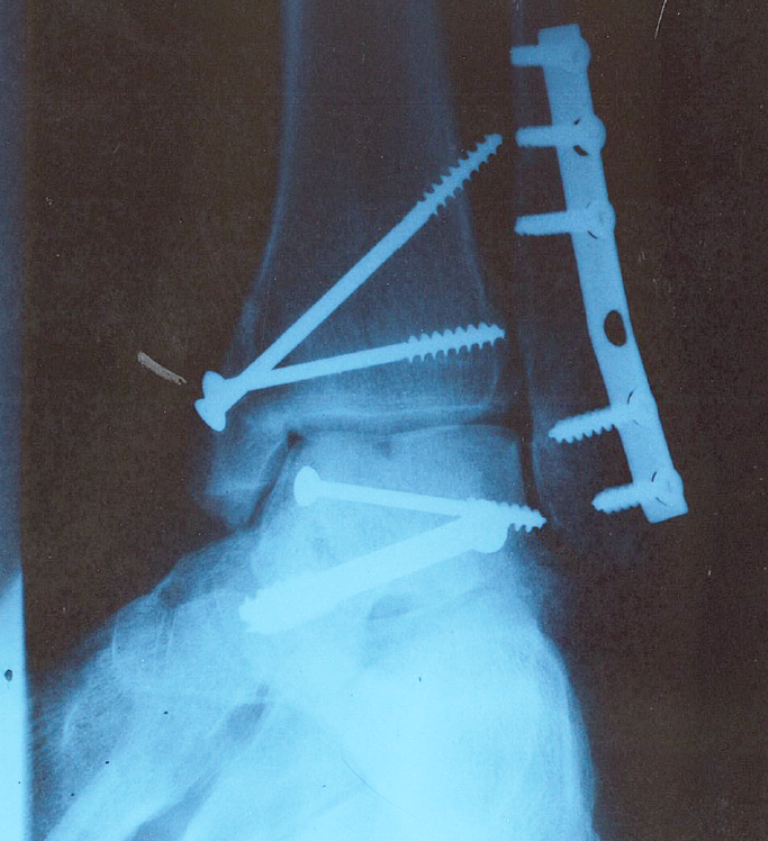

Bloody hell mate. You made a mess of that.

And I thought my right heel pain was bad.

Your photo has stopped me moaning though.

Also looks like the surgeon has raided my toolbox for screws and my posidrive screwdriver.

I think the surgeon had trouble finding the correct length screws and grabbed what ever he had.

Longer screws might work well with the shelf.